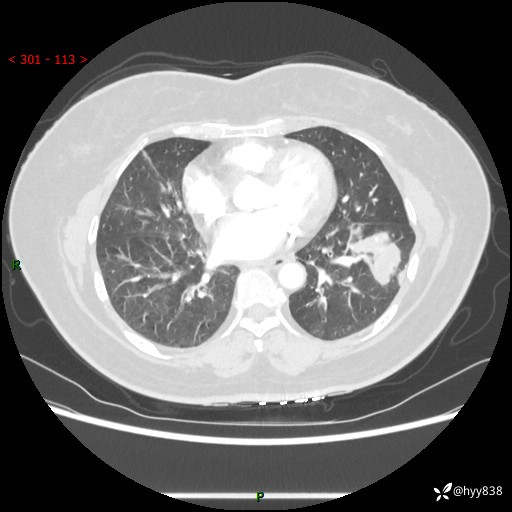

【现病史及既往史】:患者自诉2月前体检发现肺结节(左肺下叶约17mm,右肺上叶4mm),未予特殊处理,2024-10-12当地市第五医院门诊复查胸部CT提示右下肺结节(大小约3.3cm*3.9cm),患者无咳嗽、咳痰,无畏寒、发热、盗汗,无咯血,无胸闷、胸痛、呼吸困难,无恶心、呕吐,无腹痛、腹胀、腹泻等不适,现为求进一步诊治,门诊以“孤立性肺结节”收住我科。 患者本次起病来精神、食欲、睡眠尚可,大小便正常,体力、体重无明显变化。

【检查】:胸部CT增强检查